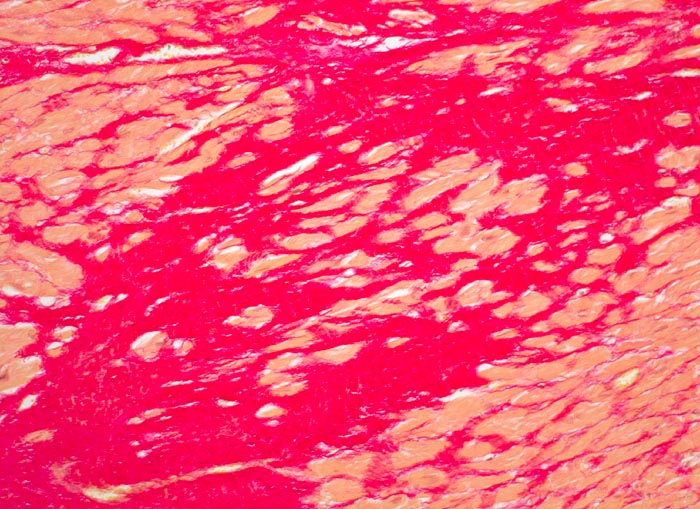

Morphologische Merkmale:

• Herdförmiger Ersatz der Muskulatur durch zellarme rote Kollagenfaserbündel.

• Hypertrophiezeichen der Herzmuskulatur im Randbereich der Narbenareale (verdickte Herzmuskelzellen mit vergrösserten hyperchromatischen Kernen).

• Im untersten Biopsiefragment sind die Narbenareale bandförmig subendokardial verteilt. Zwischen Narbengewebe und Endokard findet sich eine schmale Schicht erhaltener Muskelzellen (Ernährung dieser Zellen per Diffusion direkt aus dem Herzblut).